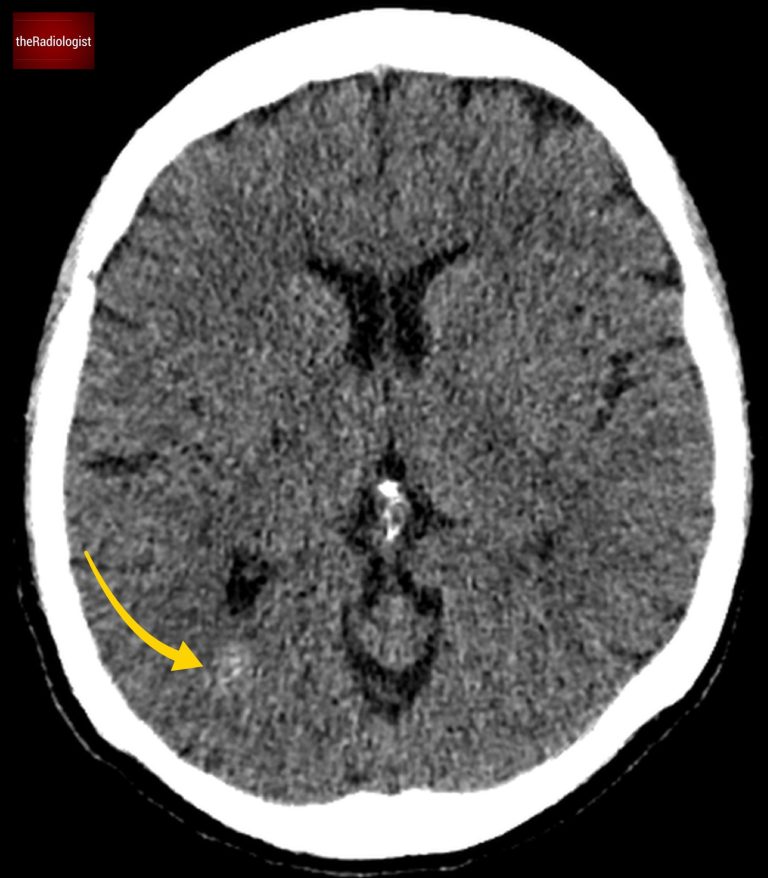

Looking at the CT scan, on first inspection there is a high density focus within the right occipital lobe. Now any high density on an acute CT head warrants suspicion for acute haemorrhage.

On closer inspection the lesion appears heterogeneous with possible flecks of calcification. There is no mass effect so the surrounding structures such as the right lateral ventricle are not distorted. Also there is no oedema (a low density rim would suggest vasogenic oedema).

Did you spot the high density lesion within the right occipital lobe?

Firstly the lesion in our case is not as dense as a typical acute haemorrhage.

There’s no surrounding oedema.

The presence of calcification further raises suspicion for something other than trauma-related haemorrhage.